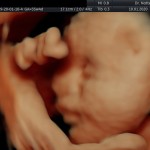

Modalidad de imagen ecográfica que permite evaluar, medir y capturar estructuras fetales superficiales e internas en 3 dimensiones (3D) y también en movimiento y en tiempo real (4D) con programas de realismo aumentado (HD LIVE) e imágenes tomografías fetales (TUI) mejorando significativamente la precisión en las mediciones fetales y la documentaciones de estructuras anatómicas.

Esta tecnología se puede utilizar desde la 6ta a la 40ma semana de embarazo.